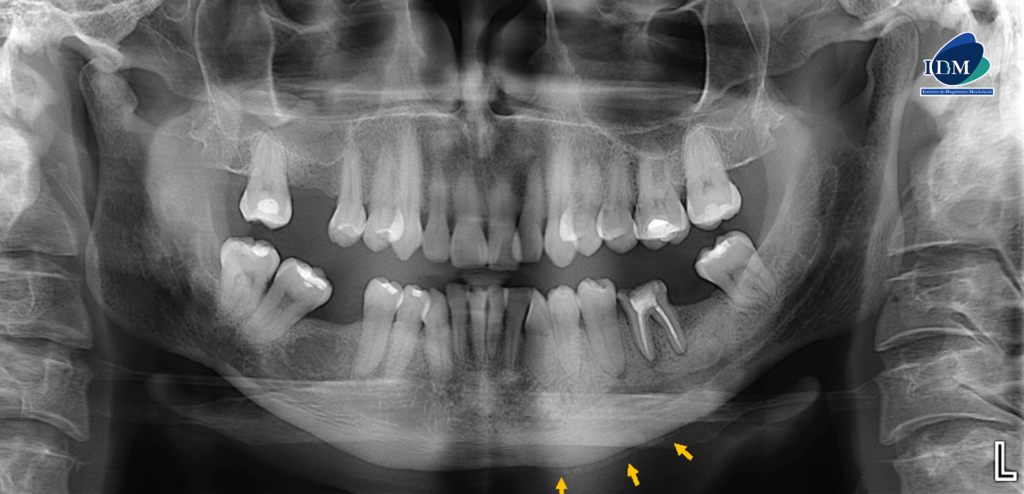

Radiografia Panorámica

En la radiografía panorámica se observa la pieza 36 con material restaurador coronario, obturación de conductos, proceso osteolítico periapical, acompañado de un aumento de la densidad ósea circundante que parece extenderse mesialmente hasta la pieza 34 y distalmente hasta la zona de la pieza 37, ocasionando el resalte del conducto dentario inferior y del agujero mentoniano izquierdo, el cual está proyectado sobre el ápice de la pieza 35. Además, se observa una reacción ósea perióstica en la basal mandibular adyacente a la zona afectada.